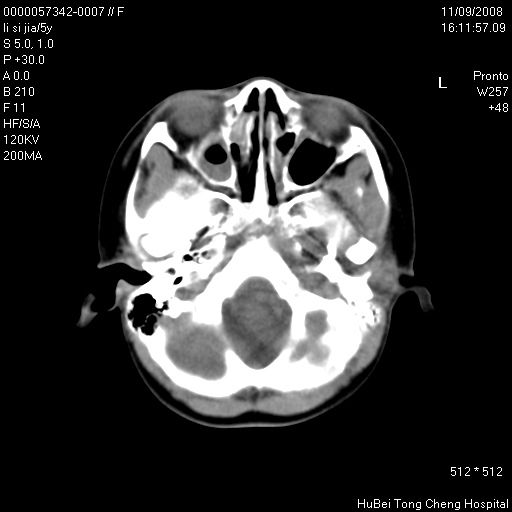

患儿 女,5岁。鼻塞、流涕2年余。

临床诊断:慢性副鼻窦炎?

副鼻窦ct轴位平扫(层厚、层距均为5mm),图像如下:

双侧上颌窦\\筛窦及蝶窦内均可见多量软组织密度影,结合病史支持考虑慢性全鼻窦炎

双侧上颌窦、筛窦及蝶窦内均可见粘膜增厚,结合病史支持考虑慢性全付鼻窦炎,腺样体肥大。